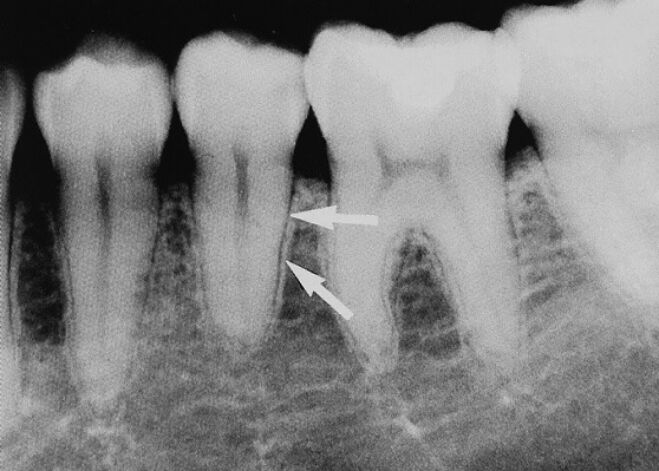

8.圖示X光片,顯示何種手術併發症? (A)拔牙傷口流血不止 (B)魯特維氏咽峽炎(Ludwig's angina) (C)局部麻醉藥注射針頭斷裂殘留 (D)下顎骨骨折

64.關於附圖影像箭頭處所指構造,下列敘述何者錯誤? (A)放射線影像學名稱為篩狀板 (B)其外觀會受放射線行進方向與皮質骨厚度之相對關係影響 (C)其外觀會受放射線行進方向與牙根之相對角度影響 (D)此一構造之厚度與牙齒承受之咬合力有關